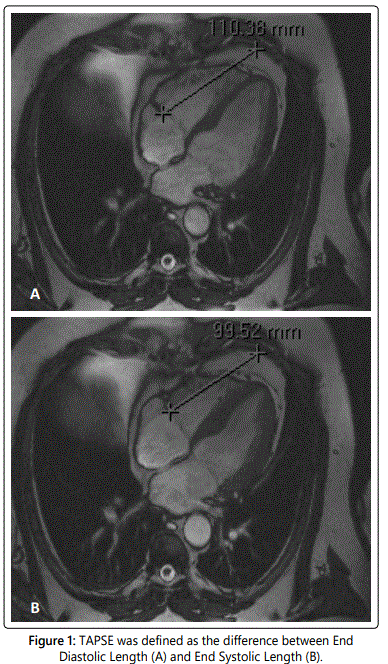

TAPSE was calculated on a four-chamber cine image using different software (Centricity Radiology RA600 v6.1, GE Healthcare, Buckinghamshire, United Kingdom). A fixed point on the thoracic wall, in line with the interventricular septum was chosen as the reference point. The distance between the reference point and the lateral side of the tricuspid annulus was measured during end-diastole (end-diastolic length [EDL] in mm) and end-systole (end-systolic length [ESL] in mm). TAPSE was defined as the difference between EDL and ESL [12] (figure 1).